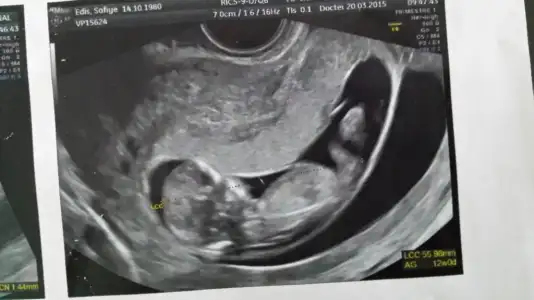

Erkeğe daha çok benzettim ikinci resimden dolayı. Ama kesin diyemem.Kızlar cinsiyet konusunda tahmin alabilirmiyim??Eki Görüntüle 1522208 Eki Görüntüle 1522219

Teşekkür ederim ben yurt dışındayım ama ultrasonda fark olurmu bilmiyorum en belirgin resmi diye koymuştum başka resim yükleyim , yorumun için çok sağol canımErkeğe benziyor ama çok değişik bir ultrason Fotoğrafı.

BANA YORUM YOKMU KIZLAR11 + 0 haftalık bebeğim yorum alabilirmiyiz

Henüz nubu oluşmamış bu teori için 12-13 haftalar en ideal zamanlar.

Bebeginiz erkek bence saglikli bi sekilde kucaginiza alin inss...